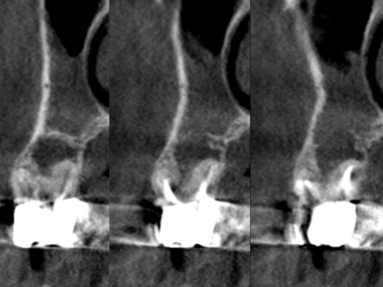

この組み合わせ3枚の写真はCT画像です。左の写真と真ん中の写真は同じものですが、わかりやすいように色を付けています。

黄色の線は根の外形です。

オレンジ色は、過去の根管治療の不備によりできた骨が吸収してしまった部分です。

赤の点線は、病変により破壊されてしまった上顎洞底(上顎洞と口の中を隔てる骨)の骨です。

水色は、それによって肥厚(腫れあがった)してしまった上顎洞粘膜です。

このような状態は2次元のレントゲンでは診断すらできません。CTを撮影することにより正確に診断ができ、それにあった処置法を選択する事が可能になります。

一番右の写真は処置直後で、MTAを用いて根管充塡し、治癒を待ちます。